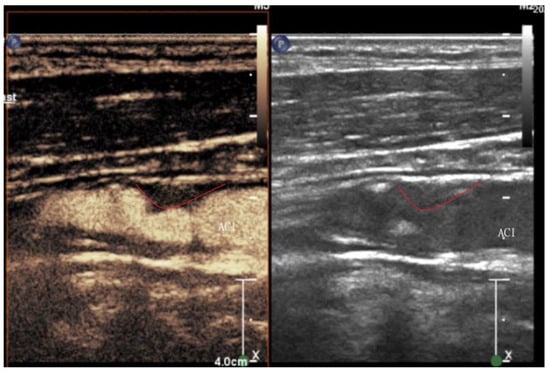

2.2. Ultrasound Characteristics

2.3. Ultrasound Contrast Agent

2.4. Principles of Contrast Ultrasound Based on Contrast Agent Pharmacokinetics